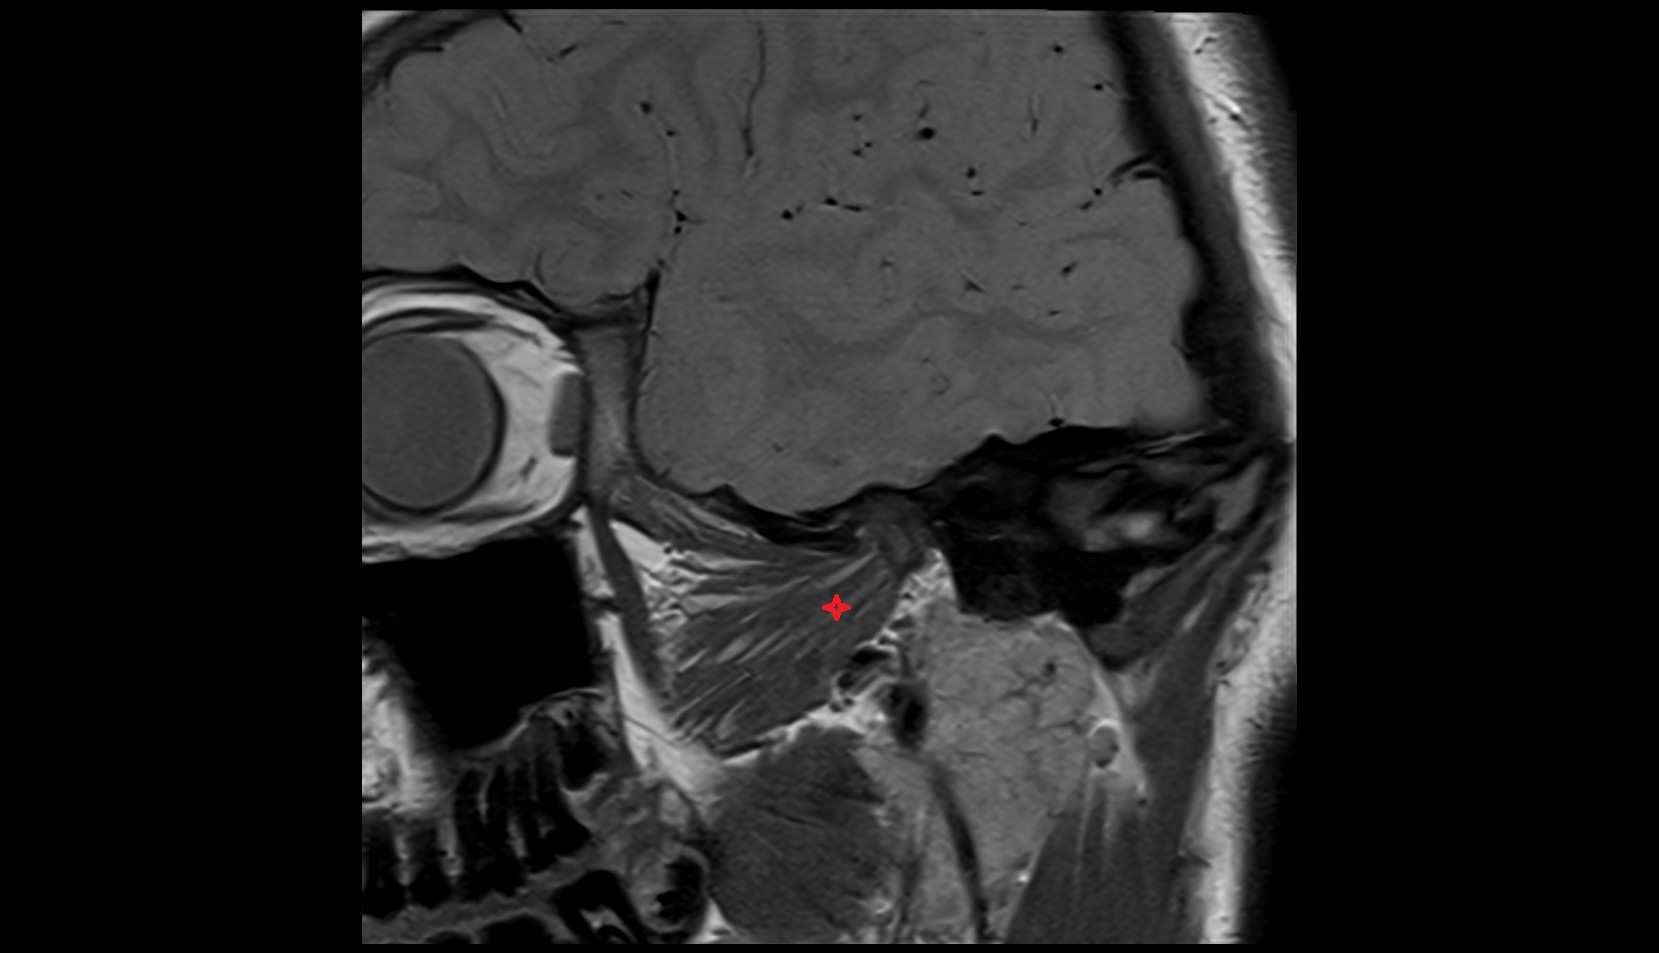

- Temporomandibular joint

- Mandibular condyle

- Mandibular fossa

- Superior head of lateral pterygoid muscle

- Inferior head of lateral pterygoid muscle

- Lateral pterygoid muscle

- Masseter muscle

- Temporalis muscle